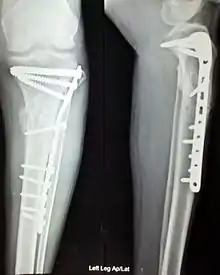

Treatment can be achieved by either non-operative (or conservative) or operative means. The main operative treatments for a Maisonneuve fracture are open-reduction surgery and closed-reduction surgery, both of which usually preceding internal fixation of the injury. These procedures are known as Open Reduction Internal Fixation (ORIF) and Closed Reduction Internal Fixation (CRIF).[6][13]

Internal fixators

Syndesmotic screws are the main, internal fixators used in surgeries for a Maisonneuve fracture. Two main types of syndesmotic screws are used: trans-syndesmotic screws (positioned at the level of the syndesmosis) and supra-syndesmotic screws (positioned above the syndesmosis).[15]

Based on several clinical results, syndesmotic screws are recommended to be fixed at least 1 centimetre proximal to the tibiofibular syndesmosis or 4 to 6 centimetres proximal to the tibiotalar joint line.[4][16] Cadaveric analyses, from a comparative study published in Foot & Ankle International in 1997, suggest that screw fixation at 2 centimetres proximal to the tibiotalar joint line is also adequate.[17] Biodegradable implants such as bioabsorbable screws, which do not require postoperative removal, may be used as an alternative to metallic hardware. However, biodegradable implants still limit rotation of the ankle and dorsiflexion of the foot.[4][6][13]

Open-reduction surgery is typically not performed at the level of the proximal fibula, as dissection near the proximal end may risk severing the common peroneal nerve. Instead, reducing the proximal fibula at the level of the distal tibiofibular syndesmosis is recommended.[6][12] A hook test is performed, using a curved hook, to assess the stability of the fibula. If instability is detected, further distraction of the fibula can be done to repair the full bone. The fibula can then be guided into the fibular notch located on the tibia, effectively restoring its length. Internal rotation of the foot may then be used to correct anatomical alignment.[12][13]

Following open-reduction, internal fixation is usually performed to stabilise the ankle mortise. To account for the distal fibula being slightly posterior to the distal tibia, drill holes are angled at 30° from the anteromedial aspect of the tibia to the posterolateral aspect of the fibula.[4][12][16] Trans-syndesmotic screws can be inserted in this way to ensure tibia fixation. Additional supra-syndesmotic screws may be temporarily inserted, for approximately 3 to 6 months, if instability is still present after fibular reduction. To reduce the fibula and restore the ankle mortise to its proper anatomical configuration, partial dorsiflexion of the foot is maintained prior to intraoperative screw fixation. This is because, in a neutral or maximally dorsiflexed position of the foot, the trochlear surface of the talus may reduce maximal postoperative dorsiflexion due to rigidity after screw fixation.[9][12]

Assessing the severity of syndesmotic lesions can be performed with fluoroscopic screening.[13] Guidance under fluoroscopy can also assist with syndesmotic screw fixation.[4] Restoration of the anteromedial joint capsule of the ankle can be achieved with suturing techniques.[7][9]